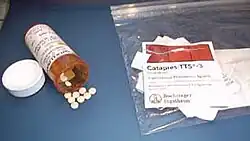

As classes de medicação com eficácia comprovada no tratamento dos tiques — os típicos e os atípicos neurolepticos — podem acarretar efeitos adversos de longo e curto prazo.[120][121] Alguns agentes anti-hipertensivos também são utilizados no tratamento dos tiques; os estudos demonstram eficácia variável, mas um perfil de efeitos colaterais inferior ao dos neurolepticos.[13] [131] Os anti-hipertensivos Clonidina e Guanfacina são geralmente testados primeiro em crianças; eles também podem auxiliar nos sintomas do Transtorno de déficit de atenção e hiperatividade,[66] [131] embora haja menos evidência de sua eficácia em adultos.[1] Os neurolepticos Risperidona e Aripiprazol são empregados quando os anti-hipertensivos não são eficazes,[3][66][120][121] e, geralmente, são testados primeiro em adultos.[1] Devido a um menor número de efeitos colaterais, o aripiprazol é preferido em relação a outros antipsicóticos.[132] O medicamento mais eficaz para os tiques é o Haloperidol, embora apresente um risco maior de efeitos colaterais.[66] O Metilfenidato pode ser utilizado para tratar o TDAH que co-ocorre com tiques, podendo ser empregado em combinação com a clonidina.[14][66] Os Inibidor seletivo de recaptação de serotoninas são utilizados para controlar a ansiedade e o Transtorno obsessivo-compulsivo.[14]